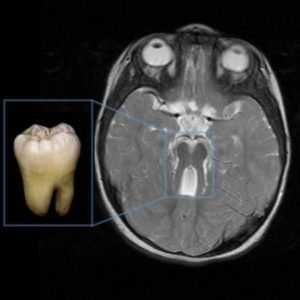

• Признак «моляра» (определяется не только на поперечном срезе МРТ, но и при УЗИ):

о Глубокая межножковая ямка:

- Дисгенезия перешейка ствола мозга → удлинение мостосреднемозгового соединения

о Утолщенные, прямые, вытянутые верхние ножки мозжечка

о Гипоплазия червя, возможна его ротация

- симптом «коренного зуба»: на МРТ в аксиальной плоскости через точку соединения среднего мозга и моста (область перешейка) выявляются признаки гипоплазии червя мозжечка и сопутствующие аномалии ствола мозга. Признак «коренного зуба» включает в себя аномально глубокую межножковую ямку, заметные, прямые и утолщенные верхние ножки мозжечка и гипоплазию червя мозжечка;

Синдром молярного зуба и другие признаки болезни Жубера на МРТ:

Диагностика с помощью МРТ продемонстрирует развитие отделов головного мозга. У пациентов с данным диагнозом наблюдаются изменения, напоминающие разрез зуба («синдром коренного зуба»). Это свидетельствует о патологических изменениях стволовой части мозга и червя мозжечка. Другими признаками недоразвития мозга являются расширенные желудочки, гидроцефалия, недоразвитие мозжечка.